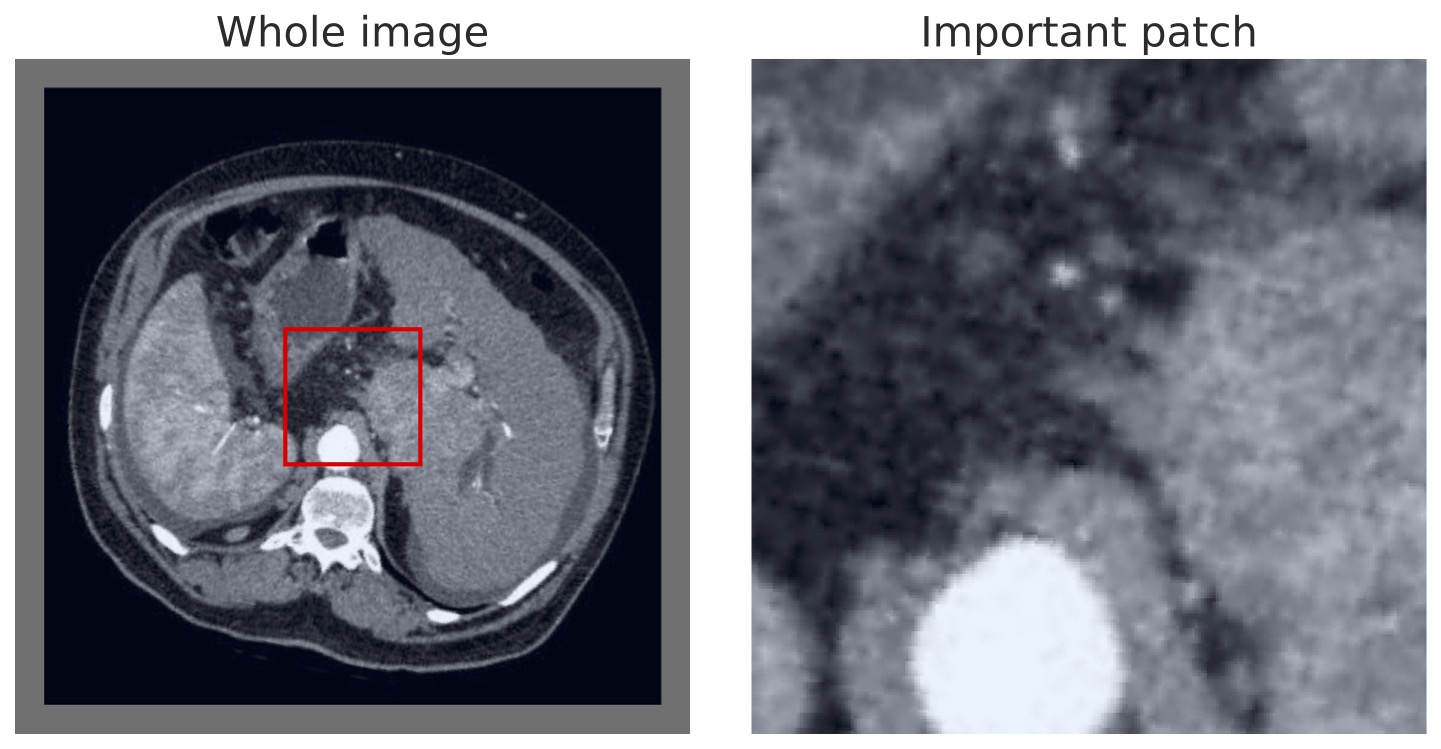

A further benefit of our approach is that the concept vectors can be used to gain an interpretable component about what the model is learning to look for. We can do this by showing example patches that correspond to the ’th concept vector activating and having the maximal response, i.e., making the classification determination. We provide an example for the first five concept classes on the BTMD dataset in Figure 4 and the RSNA-SMBC dataset in Figure 5. In both cases, the row corresponds to a concept, and 25 columns show 25 winning exemplars.

The BTMD dataset has considerably more visual variation in the images, making them more challenging to inspect as non-medical experts, but visual themes are generally discernible across each row in Figure 4. We note that there is no mechanism to force one concept vector to suppress other concept vectors for similar activations, and so we see some cross-pollination between the concept vectors. The RSNA dataset has less visual asperity, and visual patterns are more clearly observed in the rows of Figure 5.

In Figures 7 and 8, we display more representative patches selects that correspond highly to a given concept vector (one concept per row), highlighting our our method automatically learns sub-regions of the larger image space.